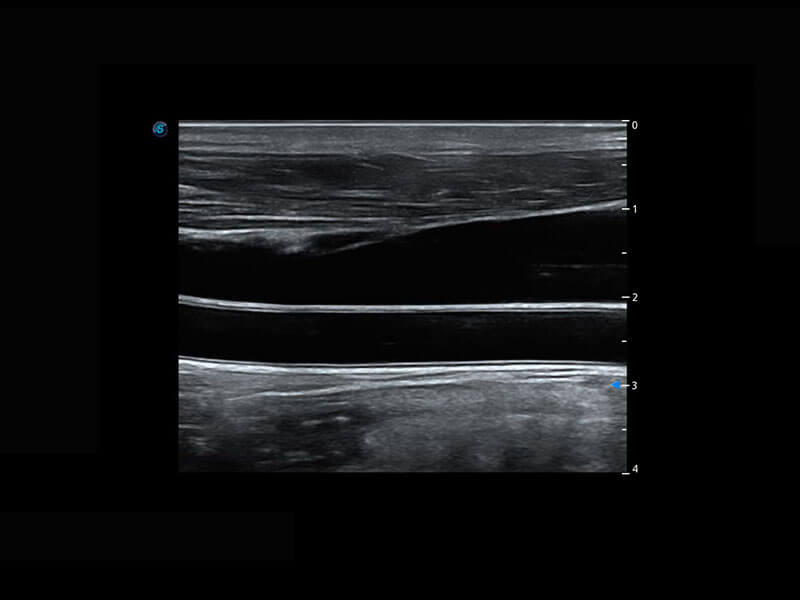

盆底超声

P60为盆底超声检查提供应用方案,多种腔内及腹部容积探头提供从二维、三维到四维的优异图像品质,实时快速三维容积数据获取,专业的测量工具包等人性化设计,为超声医生诊断提供有力保障。

S-Pelvic

能够简化盆底检查的操作流程,可在二维模式及三维成像模式下实现一键自动提取出标准切面、自动识别当前切面、自动测量,提升盆底检查的高效性,同时也能让青年医生快捷的获得准确的检查结果。